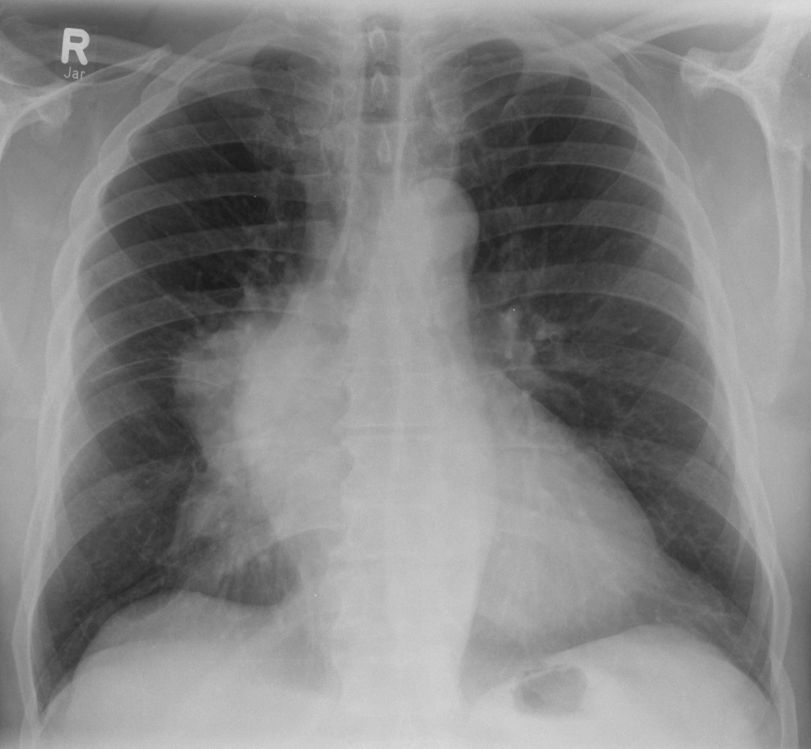

| B1-Thymom | 69-jähriger Mann, bei dem vor einer geplanten orthopädischen Operation eine Lungenaufnahme gemacht wurde. Es fand sich eine Raumforderung im vorderen Mediastinum rechts und ein kleinerer Befund rechts dorsal. Histologische malignes Thymom Stadium IV nach Masaoka. Nach 4 Zyklen Cisplatin, Doxorubicin, Cyclophosphamid partielle Remission. Nach Radikaloperation mit Pneumektomie postoperative Bestrahlung. | |||